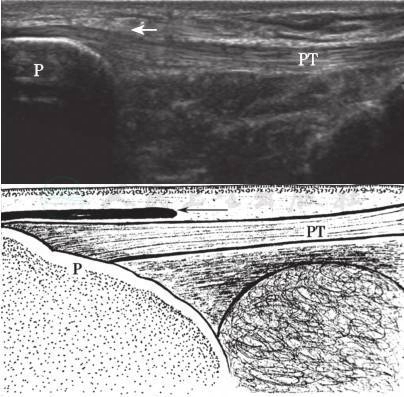

图7-10 髌前皮下囊声像图(箭)

P:髌骨;PT:髌腱

图7-11 髌下深囊声像图(箭)

T:胫骨

4.膝前部滑囊

该部位的滑囊包括髌前滑囊、髌下浅滑囊和髌下深滑囊(图7-10,图7-11)。髌前滑囊为皮下滑囊,位于髌骨下段和髌腱上1/3与皮下组织之间。髌下浅囊位于髌腱下段与皮下之间,髌下深囊位于髌腱深方与胫骨之间。正常情况下,髌下深囊内可见少量积液,不要误诊为滑囊炎。检查皮下滑囊时,探头一定要轻放,否则少量积液将会被挤压到别处。